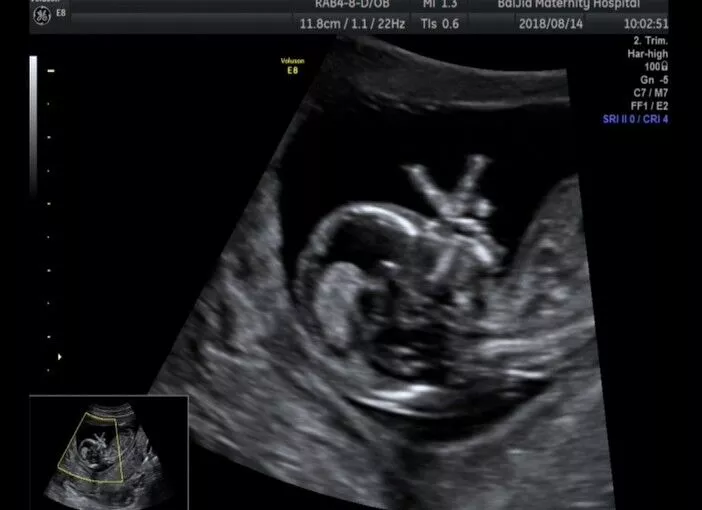

NT检查又称颈后透明带扫描,是通过B超手段测量胎儿颈项部皮下无回声透明层较厚的部位,用于评估胎儿是否有可能患有唐氏综合征的一种方法,也普遍被认为和染色体异常有关。

NT检查能检测胎儿的生长发育情况、胎盘环境、子宫状况等。

NT检查超声探头下捕捉到的

宫内宝宝欢乐场景

你们想遇见这样的宝宝吗?

确认过柔软,妈妈的这张“床”是最舒适的~

双胞胎宝宝,相亲相爱的我们~